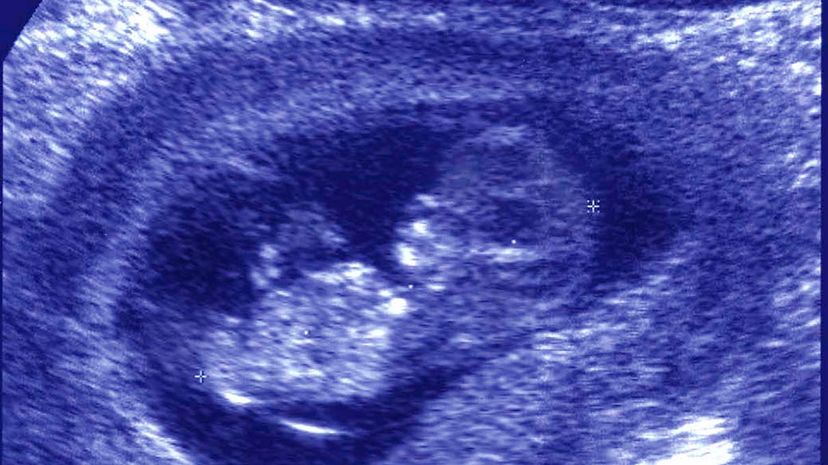

The first baby born in the U.S. from a transplanted uterus came into the world in November, and the mother's doctors at the Baylor University Medical Center in Dallas — the hospital that both performed the transplant and delivered the baby by cesarean section — are delighted by their success. This is the first birth to occur from a clinical trial involving eight women who received uterine transplants — the first ones ever performed in the U.S. Of these women, one has now given birth, one is pregnant and three others are currently trying to conceive.

The process of performing a uterine transplant is different from other organ transplants. Since the purpose of the procedure is to make sure the woman can gestate a baby for 32-36 weeks, surgeons don't really know whether the transplant has been successful until they have a baby in hand. The woman who successfully gave birth last month received her transplant in September 2016, so it took over a year to find out whether the transplant worked. The process is long, and something could go wrong every step of the way.

Transplanting the organ into the recipient is another very tricky surgery, and the healing from that operation can be a little touch-and-go — four of the transplants in this trial failed and had to be removed. In Sweden, the doctors have waited a year to allow the patient to heal, but at Baylor they waited only a few months (because the women were young and healthy, and because the antirejection drugs have some undesirable side effects). After the woman begins menstruating, she is launched into a very high-risk pregnancy, and the birth is always done by C-section.